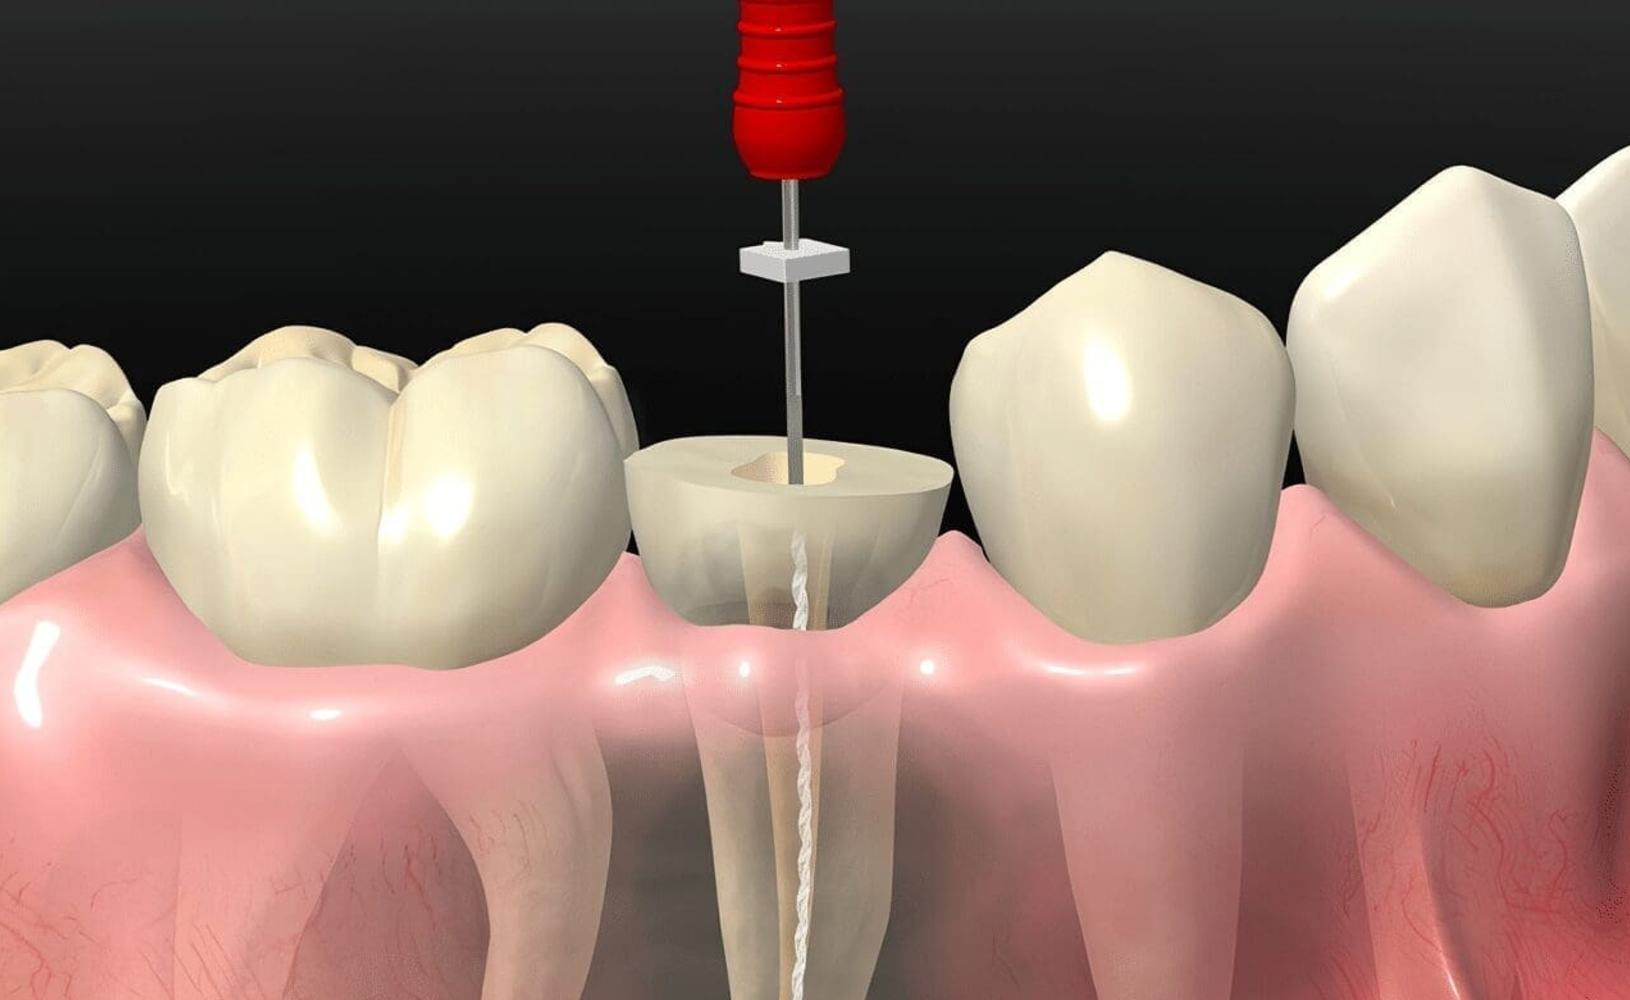

Durante el tratamiento, se aplica anestesia local para asegurar comodidad y eliminar cualquier dolor. Se realiza una apertura en la corona del diente para acceder a la pulpa, seguido de la limpieza y desinfección de los conductos. Se utilizan instrumentos de precisión y sistemas mecanizados que optimizan la limpieza, garantizando la eliminación completa de bacterias y restos de tejido infectado.

Posteriormente, los conductos se rellenan con materiales biocompatibles, como gutapercha, que sellan herméticamente los espacios y previenen reinfecciones. Finalmente, se coloca una restauración temporal o definitiva, dependiendo de la necesidad de reconstrucción posterior. Las restauraciones pueden incluir empastes, incrustaciones o coronas, asegurando la resistencia y estética del diente tratado.